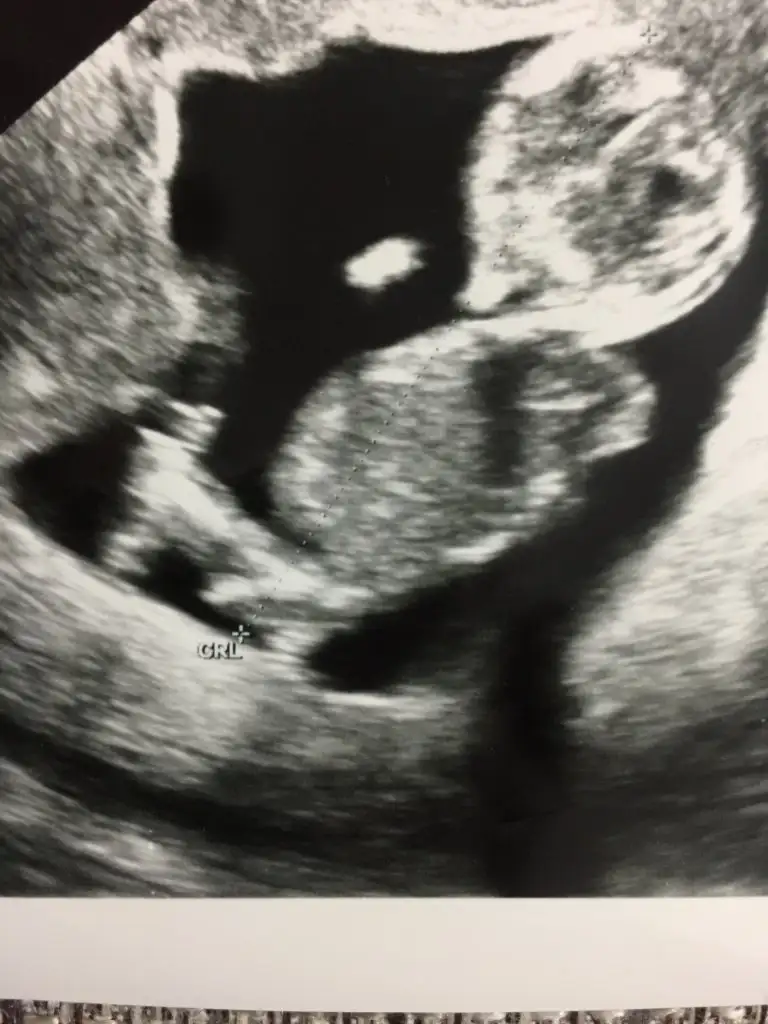

Kız gibi

Kız gibi gibi diyorum başka usg varmı varsa tahmin ederimMerhaba ben de yorum alabilir miyim 11+5Eki Görüntüle 2546031 Eki Görüntüle 2546031

Kız canım2 görüntü içinde aynı şey demi canım, doktorunda biri kız biri erkek demiş

Tahminim kızdı ögrendinizmiAy hayırlısı inşaAllah teşekkür ederiz

Evet öğrendim bugün kızım olacakmışTahminim kızdı ögrendinizmi

Saglıkla gelsin prensesEvet öğrendim bugün kızım olacakmıştahmininiz tuttu